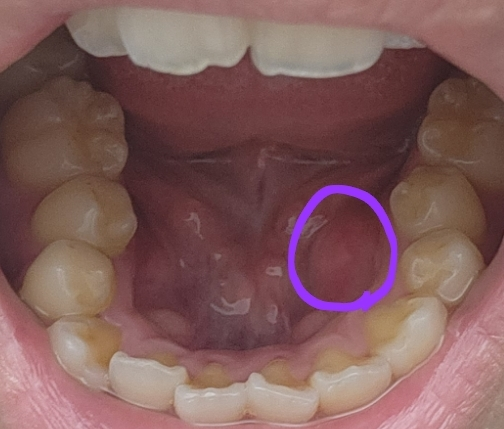

혀밑에 잇몸쪽이 엄청 부어올랐어요

사진 속 부위에 일주일 전에 구내염이 생겼었다가 지금은 다 나았거든요 그런데 엄청 부어올랐어요 사진보시면 반대편이랑 비교해도 엄청 부었는데 무슨 병인가요...?? 고통은 하나도 없어요 ㅠ

혀밑샘이 부어오른 상태로 보입니다. 침샘염은 바이러스 질환으로도 발생할 수 있지만 진료가 필요하겠으니 이비인후과를 방문해보시는 것을 권해드립니다.

구내염 이후의 부종 등이 생겼을 것 같으며

염증까지 가능성이 있기 때문에 치과 및 이비인후과에 내원하시어 진료를 받아보시는 것을 추천드립니다.